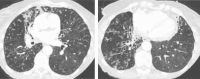

Bronchiectasis are often encountered in clinical practice, and are characterized by abnormal airway dilatation and distortion associated with impaired mucociliary clearance and mucous plugging, which are frequently associated with recurrent infections. Numerous etiologies can underlie the development of bronchiectasis, but the most important distinction in research and clinical practice is between bronchiectasis due to cystic fibrosis (CF) and bronchiectasis due to all other reasons (non-CF bronchiectasis). The causes of non-CF bronchiectasis are varied and often unclear. Patients disease severity and phenotypes of non-CF bronchiectasis also varied, which can influence disease trajectory, frequency of exacerbations and mortality. This article reviews the published evidence and suggests interventions to enhance airways clearance in patients with non-CF bronchiectasis, which are key components of an individualized therapeutic program in order to achieve symptomatic relief and prevention of exacerbations and functional decline.